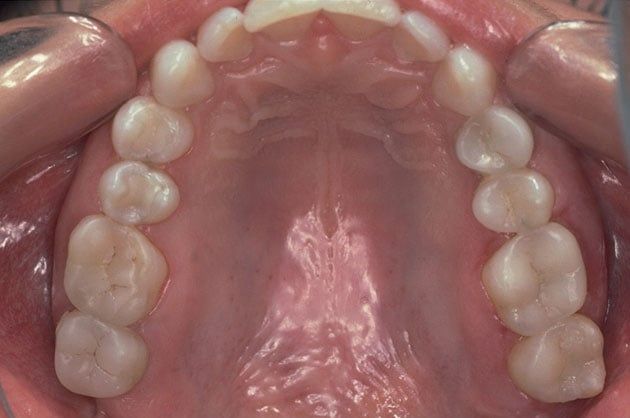

Composite fillings are today's modern filling choice. They are made to match your tooth's natural color to make them virtually invisible to notice and are placed onto the tooth by bonding the filling material to the tooth so they do not have the unlikely chance of falling off. Many patients choose to replace their old silver and gold fillings with composite fillings.

Strong and Natural Looking

White fillings are made from a high-strength composite resin that can be easily color-matched to your natural tooth making it nearly invisible to you and anyone else. Unlike silver and gold fillings, composite tooth-colored fillings actually bond to the tooth which means they support the surrounding tooth structure, which helps to prevent breakage and insulate the tooth from excessive temperature changes. You are much less likely to have a composite filling fall out which is a common issue with metal fillings.